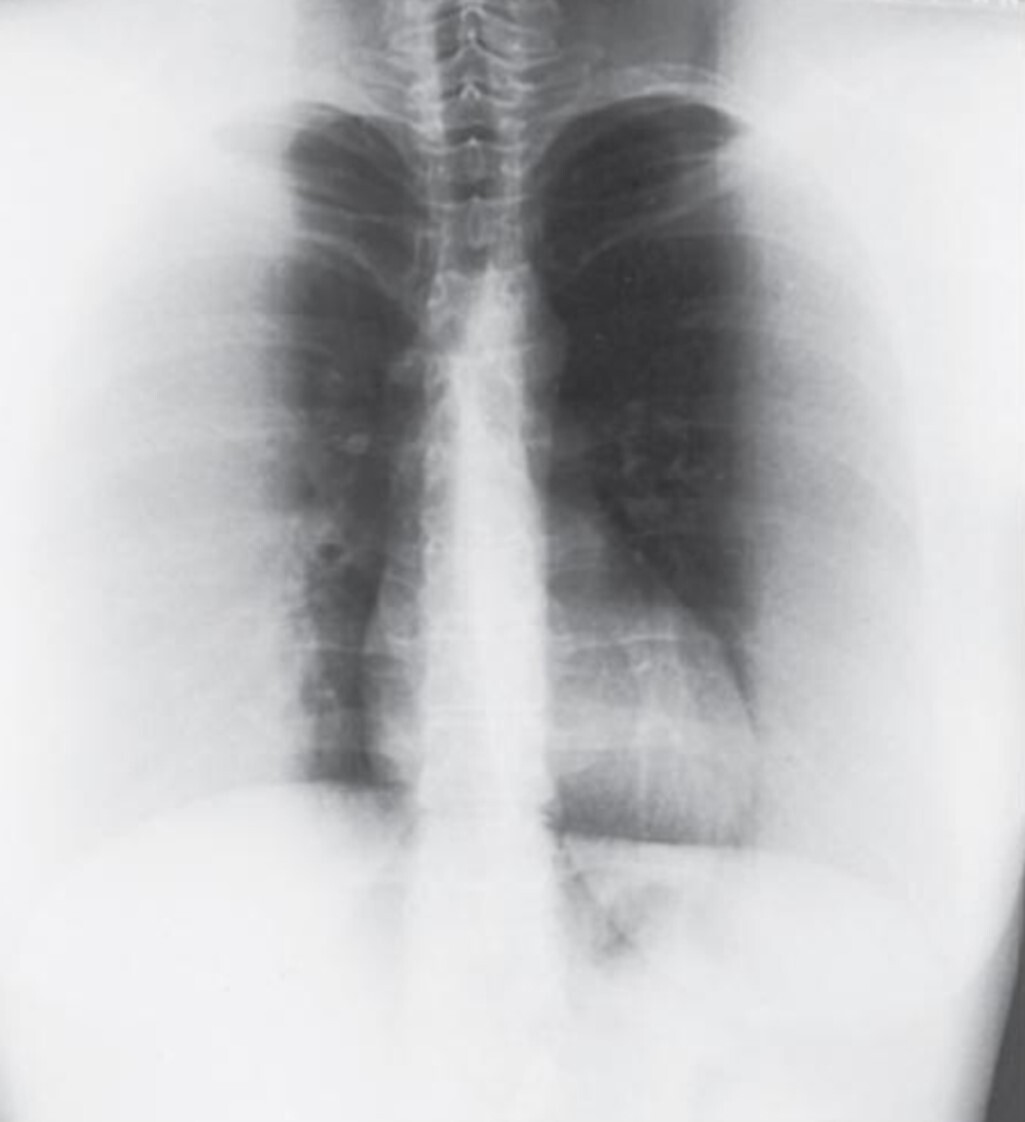

Q

What artifact is seen superimposed over the scapula and lateral chest wall in the attached image?

A

Patient artifact (bra straps)